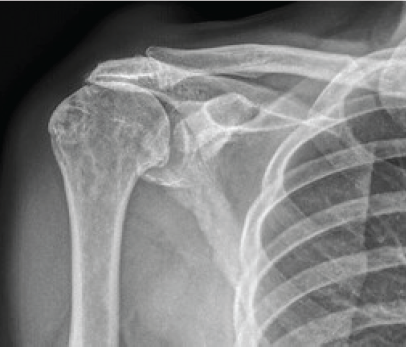

A Silent Shoulder of Plentiful Pathology: An Uncommon Presentation of Acromioclavicular Ganglion Cyst

Steve Fernandes , Santosh Jeevannavar , Keshav Shenoy , Prasanna Baindoor

………………………………p.116-120